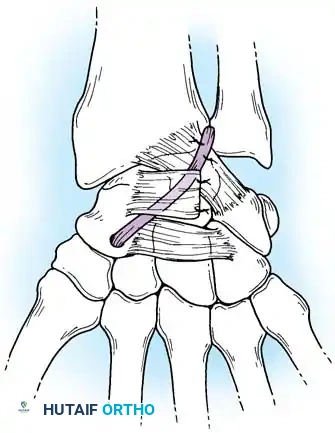

Closed reduction with percutaneous pinning (placing 0.045-inch K-wires from the scaphoid to the capitate and lunate) can be attempted. However, open reduction through a dorsal approach is generally preferred. This allows direct closure of the scapholunate gap, K-wire fixation, and primary repair of the dorsal SL interosseous ligament using suture anchors.